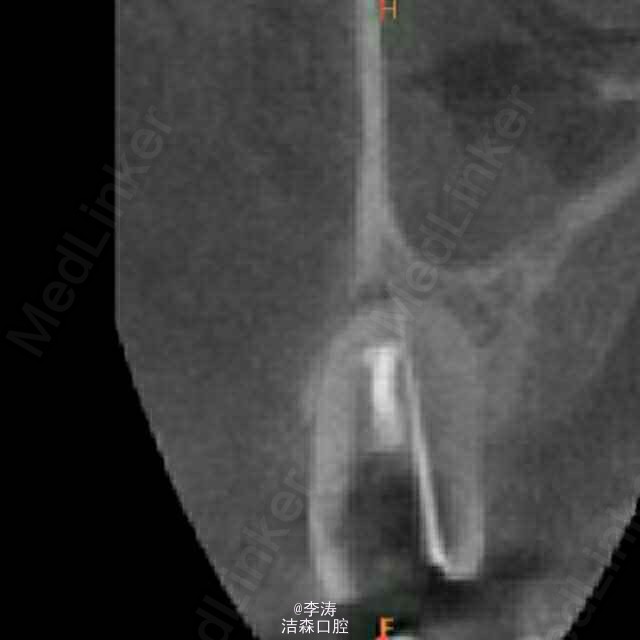

过台阶根管再治疗一例

15牙因根管治疗后牙折裂,行根管再治疗

根管预备形成台阶1例

年轻恒牙;根管再治疗;消除台阶